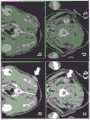

Fig. 6 depicts imaging of metastatic disease in a spontaneous melanoma mini-pig model according to an embodiment of the present invention.124I-cRGDY-PEG-C Point and Combined PET-optical imaging methods to assess SLN mapping in spontaneous melanoma mini-pig models (Mils Verl)Veterinary immunology and immunopathology (1994); oxkholdler (oxenhandle), journal of american pathology (am.j. pathol.) (1979); milliken (Millikan), journal of dermatology (J.Invest.Dermatol.) (1974)) (small sinkray pigs, center for the sinkray study). Image-guided metastatic disease detection, staging and assessment of different tumor loads in SLNs was assessed in 4 to 10kg minipigs (n ═ 5) in combination with associated histopathology. The results of these studies, described below, show that,124I-cRGDY-PEG-C relative to18F-FDG achieves excellent detection sensitivity and discriminates metastatic tumor burden within hypermetabolic neck nodules. In all piglets, 5 milliCurie (mCi) was injected systemically18Performing dynamic 1h high resolution and whole body after F-FDG18F-FDG PET-CT scan to screen for metastatic disease, followed by124I-cRGDY-PEG-C spot administration. FIG. 6a depicts the whole body18Longitudinal and axial views of F-FDG PET-CT, showing primary tumor (dark arrow) and single SLN (white arrow) in the right neck (posterior) after intravenous injection (anterior). In representative animals, hypermetabolic melanoma lesions and PET-avid right SLNs were initially identified in the posterior neck, as shown in figure 6 a. After two days, it is administered as one fourth124The I-crgd y-PEG-C site (about 0.5mCi,>95% purity), the subcutaneous dose is around the tumor site. FIG. 6b is a high resolution PET-CT scan showing a subcutaneous quarter peritumoral injection124Bilateral nodes 1 hour after I-cRGDY-PEG-C point (SLN, arrow; left node, arrow). High resolution and whole body dynamic PET scans confirmed the previous 5 minutes after injection18F-FDG imaging found that 2 PET affinity nodules were additionally identified, one on the left posterior neck and the second immediately anterior to the SLN as shown in fig. 6 b. No other PET affinity nodules or suspect tracer capture regions were seen.

Fig. 6c and 6d are gross images of the cut surface of the black shaded SLN (asterisk, c) and contralateral metastatic nodule (arrow, d) in the left posterior neck. Imaging within an exposed surgical bed is confirmed during surgery by visual inspection and prior to resection using y-count of a handheld PET deviceA nodule. FIG. 6c shows excised global nodule specimens, smaller (1.0 X0.6X1.0cm) than those shown in FIG. 6d3) The display of the posterior left PET affinity nodule was measured as 1.3X1.0X1.5cm3Black light-blocking (melanin-containing) SLN. FIG. 6e is H&E low magnification view of stained SLN, showing a diffuse melanoma cluster (white arrow), and fig. 6f is H&E stained corresponding high magnification views of SLNs, which reveal melanoma cells (yellow arrows) and melanophagous cells (white arrows). H&E-stained SLN tissue sections revealed dark melanoma clusters on the low magnification view (fig. 6E), including both melanoma cells and melanocyte-containing macrophages (i.e., melanocyte phagocytic cells) on the high magnification view as shown in fig. 6 f. These findings were similar to those of excised primary lesions (data not shown). Fig. 6g is a low magnification image of melanoma specific marker HMB-45 (white arrow) in representative SLN tissue. FIG. 6h is a high magnification image of HMB-45 stained SLN tissue. FIG. 6i is H&E stain low magnification view of contralateral lymph nodes showing scattered melanoma clusters (arrows). Fig. 6j is a high magnification image of the contralateral nodule, showing infiltration of melanoma cells (arrows). Fig. 6k is a low magnification image of representative normal pig nodule tissue. Fig. 6l is a high magnification image of representative normal pig nodule tissue. Scale bar: 1mm (e, g, i, k); tm (f, h, j, I). (adapted from journal of clinical research 2011, 121, 2768 to 2780). Immunohistochemical staining of SLN with the known human melanoma marker HMB-45 indicated positive expression of this marker on low magnification (fig. 6g) and high magnification view (fig. 6 h). In contrast, H from the left PETavid nodule&The low magnification (fig. 6i) and high magnification (fig. 6j) views of the E stained section show that a small number of smaller sized melanoma clusters contain both melanoma cells and melanophagia cells. The tumor burden in this smaller nodule (estimated to be 10 to 20 times smaller than SLN by pathological analysis) is sensitively recognized by the targeted particle probe. Representative normal appearance porcine nodule tissue harvested from the neck does not exhibit metastatic infiltration in low magnification (fig. 6k)) high magnification (fig. 61) views.

Fig. 7 depicts image-guided SLN mapping in an idiopathic melanoma mini-pig model using pre-operative PET imaging, according to an embodiment of the present invention. These studies are extended to include optical imaging using a portable fluorescence camera system along with radioactivity detection using gamma probes for performing real-time assessment of draining tumor lymphatic vessels and nodal metastases. In the representative mini-pig depicted in fig. 7, the following procedure was used18F-FDG and124initial preoperative PET-CT scans were performed at I-cRGDY-PEG-C site. Fig. 7a and b are axial CT images showing the left pelvic soft tissue cell mass (a, arrow) and the left rib SLN (b, arrow). FIGS. 7c and d are axial18F-FDG PET images showing local activity in the tumor after intravenous tracer injection (c, black arrow) and left flank SLN (d, black arrow). Axial CT images revealed primary pelvic tumors (fig. 7a) and drainage SLNs (fig. 7b), which were considered in correspondence18Areas of increased activity on the F-FDG PET scan (FIGS. 7c and d). FIG. 7e is an axial direction124The 1-cRGDY-PEG-C spot was co-registered with PET-CT images showing local injection sites around pelvic foci (e, white arrows). FIG. 7f is a coronal plane1241-cRGDY-PEG-C dots were co-registered with PET-CT images showing local injection sites around pelvic foci (e, white arrows). Fig. 7g is a co-registration PET-CT image localization activity (g, white arrow) for the axial coronal plane of SLN and includes large bladder capture evidence corresponding to fig. 7 e. Fig. 7h is a coronal co-registration PET-CT image localization activity (g, white arrow) for SLN and contains large bladder capture evidence corresponding to fig. 7 f. Figure 7i depicts the degree of radioactivity in a primary tumor, SLN (in vivo, ex vivo), and a site distant from the primary tumor (i.e., background) using a handheld gamma probe. These findings were made 2 days later by injecting a quarter of the injection subcutaneously around the tumor site124Confirmed by dynamic PET-CT imaging about 5 minutes after I-cRGDY-PEG-C point; co-registered axial (fig. 7e and 7g) and coronal (arrow, 7f, 7h) views indicate these findings. After pre-operative scanning, the skin covering the SLN site is marked for intra-operative positioning, and the mini-pig is transported to the operating room. Use of a portable gamma probe in the treatment of primary tumors andbaseline activity measurements made at the SLN site (fig. 7i) showed a 20-fold increase in activity within the SLN relative to background signals.

Fig. 8 depicts image-guided SLN mapping in a spontaneous melanoma mini-pig model showing real-time intra-operative optical imaging of relevant histology, in accordance with an embodiment of the present invention. Intraoperative SLN mapping was performed on the animals shown in fig. 7. Figures 8a to i depict two-channel NIR optical imaging of exposed nodule basins. Fig. 8a depicts the locally injected RGB color (green) of the particles incorporating cy5.5 displayed in the two-channel model. Fig. 8b depicts NIR fluorescence channels (white) with injection of particles incorporating cy5.5 shown in the two-channel model. Fig. 8c to f depict drainage lymph vessels distal to the injection site. Fig. 8f depicts fluorescence signals within the lymphatic channels (arrows) at the distal major drainage end (fig. 8f) extending towards the SLN ('N'). Smaller bore channels (arrows) are also shown. (fig. 8g) images of SLNs are displayed in color and (fig. 8h) NIR channels. Fig. 8i depicts a color image of exposed SLNs. Fig. 8j to m show SLN images in the color and NIR channels during ablation (fig. 8j, k) and after ablation (fig. 8I, m), respectively. Fig. 8n depicts a low magnification view of H & E stained SLN and shows the clustering of shaded cells (black box) (scale bar 1 mm). Fig. 8o shows a higher magnification of fig. 8n, which shows rounded shaded melanoma cells and melanophagous cells (scale bar 501. tm). Fig. 8p shows a low magnification view of HMB-45 stained (dark area) SLN confirming the presence of metastases (black box, scale bar 5001. tm). Figure 8q depicts a higher magnification in figure 8p demonstrating clustering of HMB-45+ expressing melanoma cells (scale bar 1001. tm).

For real-time optical imaging of the lymphatic system, administered around a tumor site with intact skin124A second subcutaneous injection of I-crgd y-PEG-C spot and signal was examined in the color and cy5.5 fluorescence channel, which are depicted in fig. 8a and 8b, respectively. Adjacent nodule basins were exposed and fluorescence signals were seen in NIR channels flowing from the injection site (depicted in fig. 8 c) into the main proximal (fig. 8c and d), intermediate (fig. 8e) and distal (fig. 8f) lymph branches, which drained towards the SLN depicted in fig. 8 f. Smaller caliber lymphatic channels also appear and are depicted in fig. 8d and e. In FIGS. 8j to 8Before the continuous knot depicted in m is cut off, the black mask SLN viewed in the dual channel mode is further exposed as shown in FIG. 8i (depicted in FIGS. 8g and 8 h). The fluorescence signals in the nodule specimens in situ (FIG. 8k) and ex vivo (FIG. 8m) were confirmed by gamma emission using gamma probes (FIG. 7i), and the signals were seen to correspond to those from H&E stain scattered tumor cell clusters on low magnification (box, fig. 8n) and high magnification (fig. 8o) views of the tissue sections. Consistent with metastatic melanoma, positive expression of HMB-45 was identified on low magnification (fig. 8p) and high magnification (fig. 8q) views.

FIG. 9 depicts a pass comparison according to an embodiment of the invention18F-FDG with124I-cRGDY-PEG-C dot tracers to differentiate inflammatory and metastatic disease. FIGS. 9 a-d depict the use of18F-FDG-PET is associated with tissue-related inflammatory imaging changes. FIG. 9a depicts18Axial CT scans of the F-FDG PET study showed calcification in the left posterior neck (yellow arrow). FIG. 9b shows a fusion axis18F-FDG PET-CT exhibits hypermetabolic activity at this same site (arrow). Increased PET signals were also seen in metabolically active bone structures (asterisks). FIGS. 9c and 9d depict H&E low and high magnification views of stained calcified tissue indicate extensive infiltration of inflammatory cells. FIGS. 9e to k depict injection around a tumor site124Detection of metastatic disease after I-cRGDY-PEG C-point. FIG. 9e shows124Axial CT scan before I-crgy-PEG-C spot injection showed calcified soft tissue in the posterior neck (arrow). Figure 9f depicts that co-recorded PET-CT did not show significant activity corresponding to calcified regions (arrows), but indicated PET affinity nodules on the right side (arrows). Fig. 9g depicts axial CT at a more superior horizon showing bilateral nodules (arrows) and calcific foci (arrows). FIG. 9h depicts fusion PET-CT indicating PET affinity nodules (N) and lymphatic drainage (curved arrows). Calcification showed no activity (arrow). Fig. 9i and 8j depict low and high (fig. 9j) magnification views confirming the presence of nodule metastases. Figure 9k depicts a single frame from three-dimensional (3-D) PET image reconstruction showing multiple bilateral metastatic nodule (arrows) and lymphatic channel (solid arrows) drainage injection sites (white asterisks). Bladder activity was seen (dotted arrow), but notTo significant tracer accumulation in the liver (black asterisks). Bladder activity was seen, but no significant tracer accumulation in the liver was seen. The scale in fig. 9c and 9d represents 500gm and the scale in fig. 9i and 9j represents 100 gm. Unexpectedly, and as observed18F-FDG found in comparison to124The I-cRGDY-PEG-C spot specifically distinguished metastatic tumor infiltration from inflammatory processes in these minipigs. The mechanistic differences in the behavior of these agents at the cellular and sub-cellular levels, as well as the presence of integrin targeting moieties on the particle surface, may explain the imaging findings observed. In a number of miniature pigs containing pathologically documented inflammatory changes due to granulomatous disease (n-3),18F-FDG fails to detect metastatic disease, although inflammatory and other metabolically active sites are identified. These differences find out to highlight124The ability of the I-cRGDY-PEG-C site to selectively target, localize metastatic disease and stage, while in most cases18FDG cannot accurately stage cancer spread and in fact only identifies inflammatory sites.

In a representative mini-pig study illustrating these findings, the initial axis was18The F-FDG PET-CT scan showed calcification in the upper left back neck of CT (FIG. 9a), corresponding to18The region of strong activity on F-FDG PET (FIG. 9 b). FIGS. 9c and 9d depict H, respectively&Low and high magnification views of E-stained tissue sections revealed diffuse inflammatory changes consistent with granulomatous disease. FIGS. 9a and 9b depict the additional strong findings seen in the metabolically active bone marrow compartment of these young piglets18F-FDG PET activity. In contrast to this, the present invention is,124I-cRGDY-PEG-C point imaging research identifies bilateral metastatic cervical lymph node. See on co-registered PET-CT that the right neck nodule on axial CT imaging (fig. 9e) is PET hypermetabolism (fig. 9 f); the extra bilateral lymph nodes on the superior CT image (fig. 9g) were also PET hypermetabolized on the fused PET-CT (fig. 9 h). Furthermore, left-side cervical calcification as depicted in fig. 7e and 9g showed no PET activity on the co-registration scan, as depicted in fig. 9f and 9 h. Corresponding to H&E-stained SLN tissue sections exhibited low magnification (box, fig. 9i) and high magnification views (bFig. 9j) dark melanoma clusters seen to consist of melanoma cells and melanophagous cells. A single box (fig. 9k) selected from the 3D PET reconstructed images again illustrates multiple bilateral PET-avidity cervical lymph nodes and associated draining lymph channels. Importantly, most activity was seen in thebladder 1 hour after injection, with no significant tracer accumulation on the liver region.